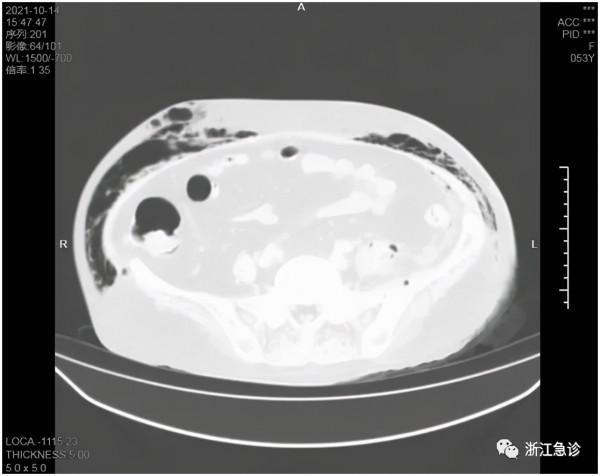

患者女性,53歲,1周前自己發現左側會陰面板紅腫,沒有引起重視,過了二天紅腫範圍增大,觸之有壓痛,活動後明顯,伴乏力,活動受限,有腹痛不適,無發熱,無腹瀉,無噁心嘔吐等不適。患者原有高血壓、糖尿病及肝血管瘤手術史。到了第三天,因為病灶擴大迅速,就到當地醫院就診,這時患者整個胸腹部面板出現瘀點瘀斑,胸部CT發現廣泛縱膈氣腫及左側腹膜後氣腫;還有兩肺炎症及左側胸腔少量積液,也就是說,病灶從左側腹股溝一直波及到腹、胸、縱膈及背部。這下嚇壞了當地醫師。因為從來沒有見過如此嚴重的病例,感到問題嚴重,就轉到縣級市人民醫院。當地人民醫院發現炎症很嚴重(血常規+超敏C反應蛋白:WBC 9.1+10^9/L,Hb 129g/L,PLT 135+10^9/L,CRP 330.83mg/L),同時已經出現呼吸衰竭的傾向,急轉來我院。急診又做了全腹部CT和頭顱CT,頭顱CT正常,腹壁下有廣泛的積氣積液,立即收住入急診ICU。